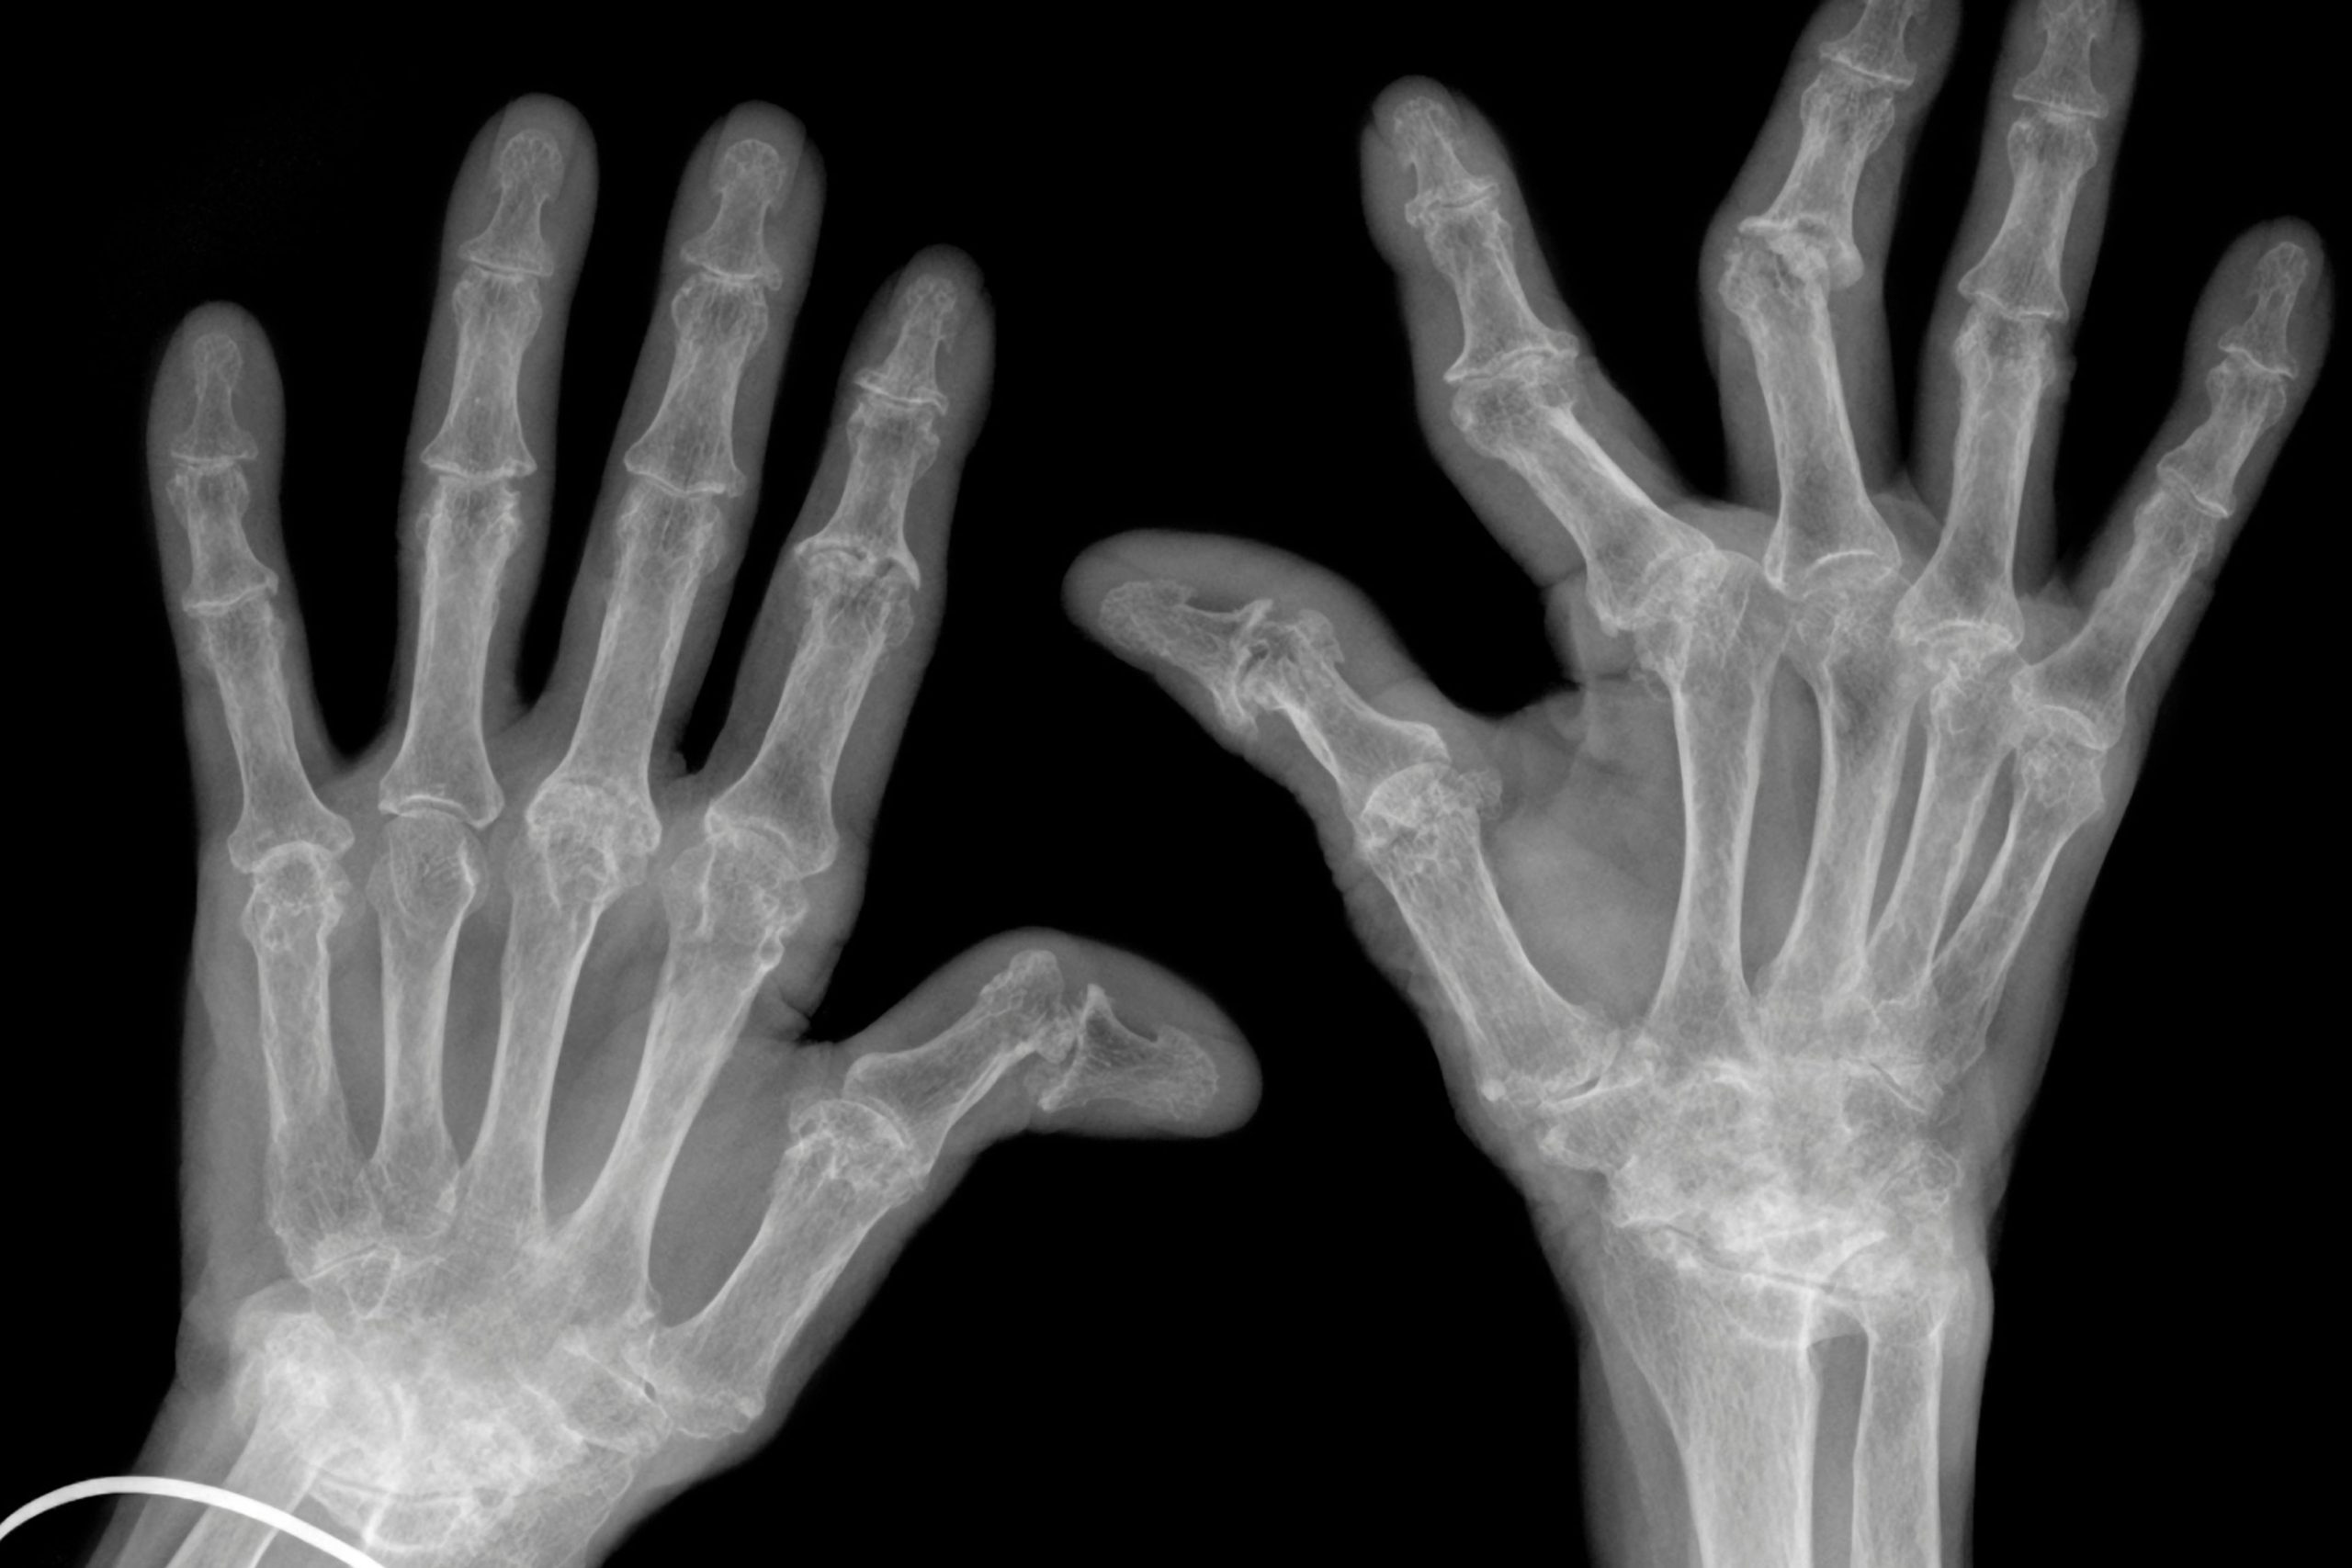

Nelle malattie reumatologiche quali l’artrite reumatoide il grasso in eccesso può diventare un pericoloso alleato dell’infiammazione. Eppure oggi fino al 50 per cento dei pazienti con artrite reumatoide e addirittura il 60 per cento di quelli con artrite psoriasica presenta sovrappeso o obesità.

«L’obesità è un fattore di rischio riconosciuto per alcune malattie reumatologiche come l’artrosi ed è coinvolta nella patogenesi dell’artropatia psoriasica. È, inoltre, un fattore complicante dell’artrite reumatoide – spiega Roberto Felice Caporali, presidente eletto SIR – Chi presenta una malattia reumatologica e ha anche un BMI elevato, in genere, va incontro a una condizione più severa e risponde meno efficacemente ai farmaci. A spiegare questa relazione sono due elementi. Oltre al ben noto effetto meccanico (cioè l’aumentato stress su articolazioni già compromesse) sta emergendo un altro aspetto, meno visibile ma altrettanto rilevante: l’impatto immunologico dell’eccesso di tessuto adiposo. Il problema, insomma, non è soltanto portarsi dietro più chili, ma gestire un ospite capace di dialogare con il sistema immunitario, aggravando lo stato infiammatorio».